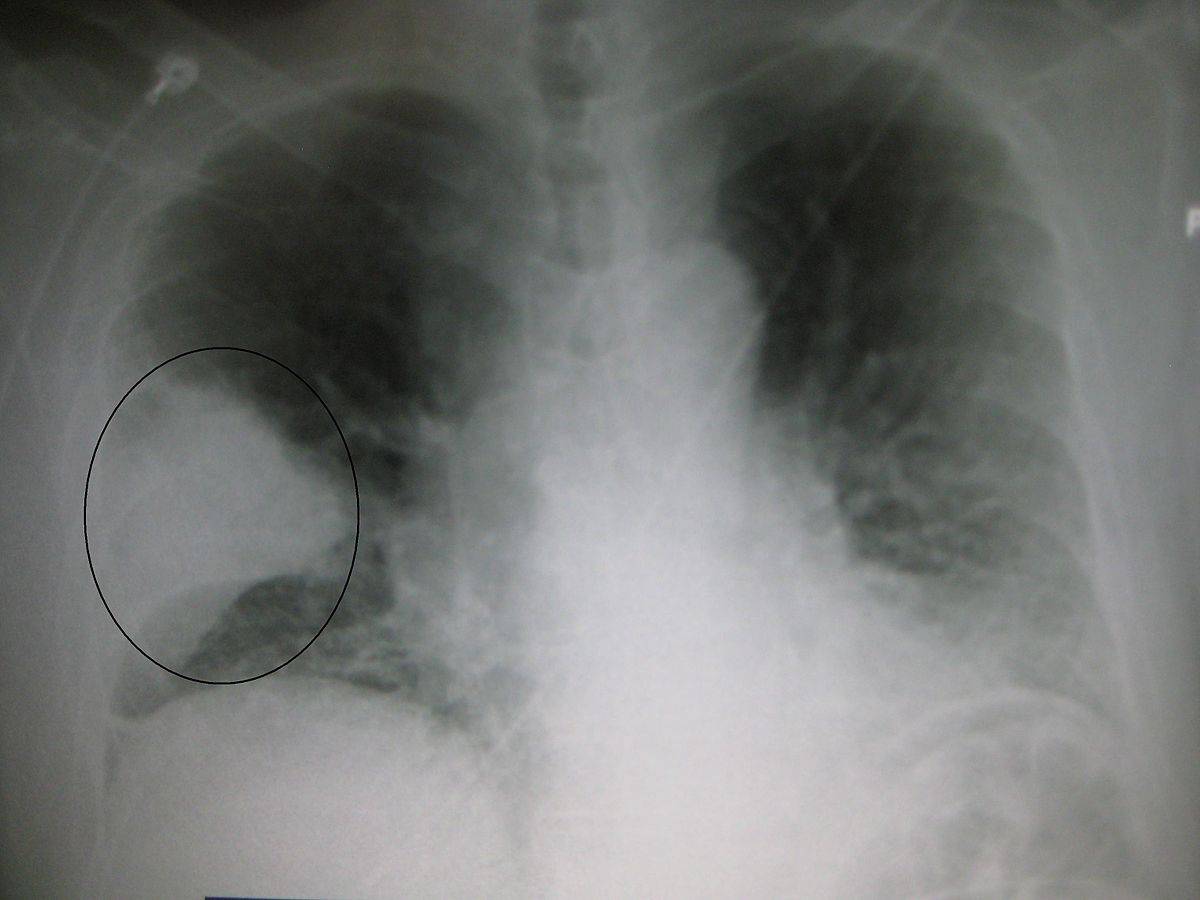

На рентген-снимке показана очаговая пневмония.

Очаговая пневмония

Очаговая пневмония встречается чаще всего, она переносится легко, если вовремя начать лечение. Нам часто задают вопрос о том, как выглядит очаговая пневмония на фото, вот её характерные особенности, которые можно увидеть на снимках:

- появление теней и значительное нарушение прозрачности на некоторых ограниченных участках;

- значительно увеличенный в размерах корень легкого, но только на той стороне, где наблюдается поражение;

- сильная деформация и усиление легочного и бронхиального сосудистого рисунка.